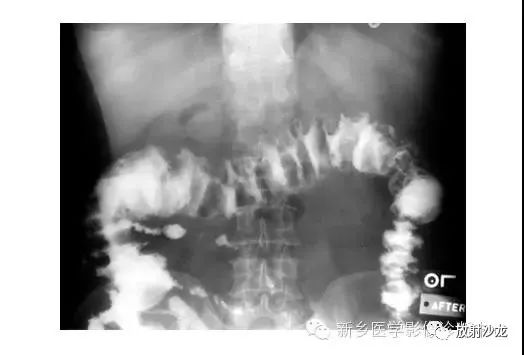

逆行通过肛管后所行X光片所示,证明了乙状结肠襻和正常肠道结构压力减低。